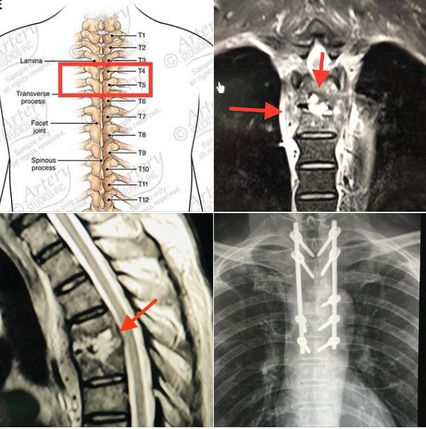

ผู้ป่วยให้ประวัติว่า พี่สาวเคยเป็นวัณโรคปอด 1 ปีก่อน และปฏิเสธการใช้ยาเสพติด ผลตรวจร่างกายปกติ แขนขาไม่อ่อนแรง ตรวจเลือดพบเลือดจางเล็กน้อย เม็ดเลือดขาวปกติ เอกซเรย์ปอดปกติ ทำคลื่นแม่เหล็กไฟฟ้ากระดูกสันหลังส่วนอก (MRI thoracic spine) กระดูกสันหลังส่วนอก (thoracic spine) ชิ้นที่ 4 และ 5 และหมอนรองกระดูกบางส่วนถูกทำลาย และสงสัยมีการอักเสบเนื้อเยื่อรอบๆกระดูกสันหลังส่วนอกชิ้นที่ 4 และ 5 ร่วมด้วย

64eea84b5cf638.82354621.PNG

แพทย์วินิจฉัยว่าเป็นโรค Spondylodiscitis กระดูกสันหลังและหมอนรองกระดูกสันหลังติดเชื้อแบคทีเรีย Staphylococcus aureus ให้ยาฆ่าเชื้อ Cloxacillin ทางเส้นเลือดและทำการผ่าตัดเอาเนื้อตายจากหมอนรองกระดูกสันหลัง ส่วนอกชิ้นที่ 4 และ 5 ใส่สกรูยึดกระดูกสันหลังชิ้นที่ 2,3,5,6,7 ส่งหมอนรองกระดูกสันหลังเพาะเชื้อ พบเชื้อแบคทีเรีย Staphylococcus aureus ตัวเดียวกับในเลือด ให้ยาปฏิชีวนะทางเส้นเลือดนาน 8 สัปดาห์ คนไข้ดีขึ้น ไม่มีไข้ ไม่ปวดหลัง เดินได้ดีขึ้น